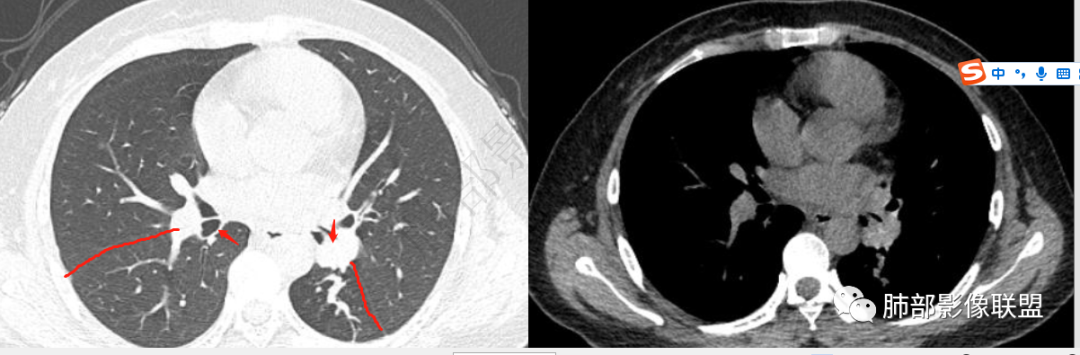

青年女性,间断咳嗽、咯血3年,再发半天,炎性指标、血沉全正常。左下肺近肺门结节,跨叶裂,膨隆分叶,支气管门口截断,平扫密度高,有钙化,增强后强化明显,未见明显坏死及淋巴结肿大,稍远端支气管内低密度影,增强化强化不明显,左下叶后基底段胸膜下结节,内有小空洞,强化明显。思路:一、感染性病变:1、整体一元考虑结核,病史反复三年咳嗽,咯血三年支持,左肺门病灶跨叶伴远端支气管内粘液栓及左下肺胸膜下伴小空洞结节均支持,疑点:前两次发作抗感染治疗均有效好转,本次炎性指标及血沉等均正常不好解释。支气管门口截断不好解释,反复发作三年,无肿大淋巴结不好解释。2、慢性非特异性炎伴机化。病史三年反复,发作时抗感染治疗有效,要考虑。二、肿瘤:1、腺癌,肺门区及胸膜下多中心腺癌,膨隆、分叶,支气管门口截断,强化明显均支持,胸膜下结节强化明显支持,反复发作的症状考虑合并阻塞性炎症。2、类癌,平扫密度较高,有钙化,强化明显支持,3、涎腺类肿瘤,性别年龄要考虑,但增强明显较均匀强化不太支持。4、淋巴瘤,影像表现要考虑,但这个年龄段的淋巴瘤一般为HD,这个不符合。所以可能小。5、极端的二元肿瘤,肺门区类癌,胸膜下腺癌。三、非肿瘤非感染性病变,血管炎,反复发作三年的症状,有过敏性鼻炎,要考虑,需要查血管炎三项和副鼻窦情况排除。临床很简单:下一步EBUS穿刺肺门区及经皮穿刺胸膜下结节。至于读片嘛,还是先考虑恶性(腺癌>类癌>二元癌>淋巴瘤),鉴别诊断:结核>非特异性炎伴机化>血管炎

然后它跟远端病灶的关系,外面病灶引起肺门区病灶,还是肺门区病变导致远端病变。

然后就是前后的变化,三年前或者一年前有什么差异,这个是我们判断的最基本的依据,但是这个缺失,造成方向不明晰,就是猜测,有可能是这种可能,有可能是那种可能。

还算不错,考虑恶性在前。只是把腺癌放类癌前面了。

肺门区肿块的恶性征像还是比较明确(膨隆,分叶,支气管门口截断,强化明显,平扫密度高,有钙化,比较符合类癌),只是有跨叶,又有远端的干扰(阻塞性粘液栓),还有胸膜下结节(现在有了结果,这个胸膜下结节应该是反复阻塞性炎后的OP改变),考虑的就要多些。

回顾,支气管阻塞,密实软组织结节灶,有强化,肿瘤还是首选

年轻女性  肺门旁   与支气管关系密切  钙化  强化明显  咯血  病史长

低度恶性肿瘤 →类癌